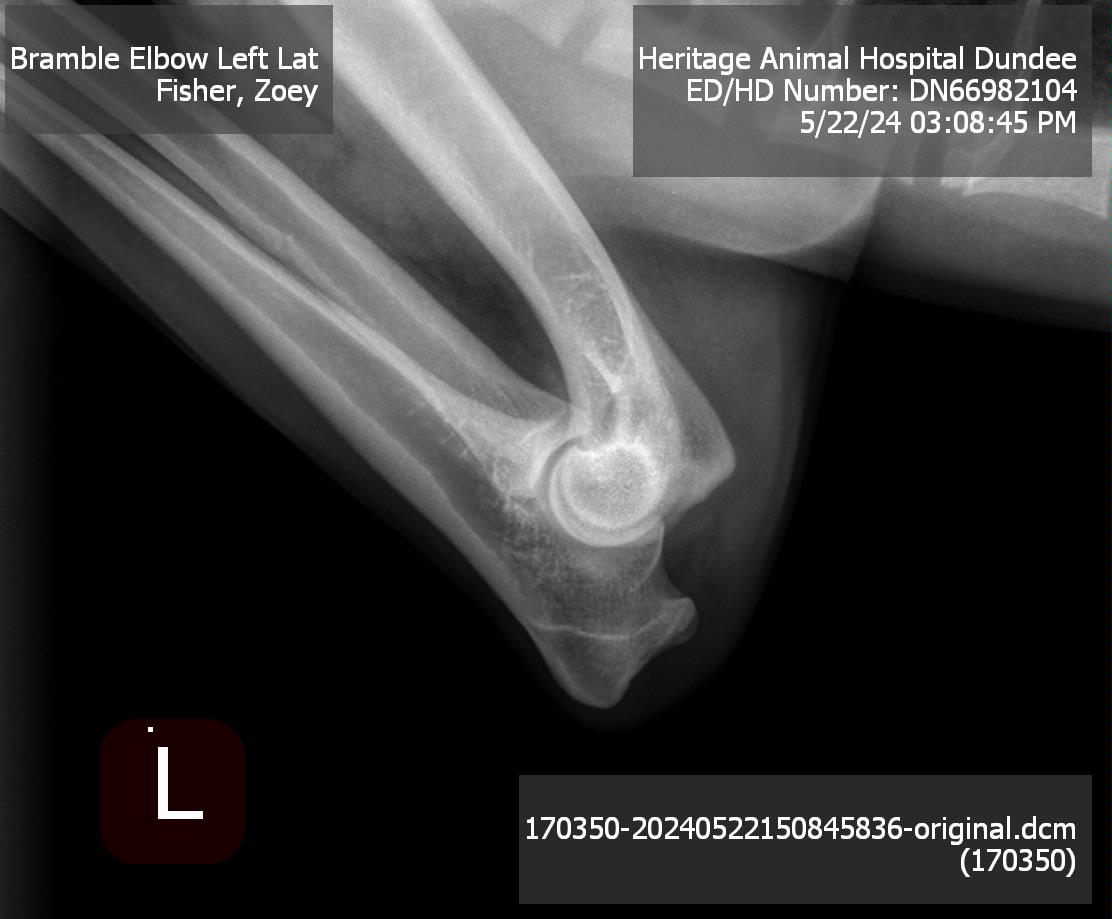

Elbows: |

Normal |

Pedigree | OFA Database Entry | Hips | Left Elbow | Right Elbow